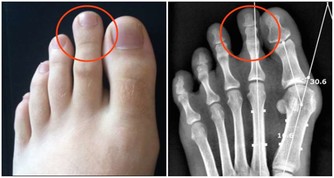

頭髮七大問題 1青壯年「少白頭」

青壯年甚至少年長白髮稱「少白頭」。後天性少白頭引起的原因很多:營養不良,如缺乏蛋白質、維生素等,以及焦慮緊張的情緒都會使頭髮變白,另外甲狀腺機能失調等也可致灰白髮。

2黃褐色或淡黃色

甲狀腺功能低下,高度營養不良,重度缺鐵性貧血和大病初癒等,導致機體內黑色素減少,使烏黑頭髮的基本物質缺乏,黑髮逐漸變為黃褐色或淡黃色。

3患某種疾病導致的

如患系統性硬皮病,系統性紅斑狼瘡時頭髮不僅會變黃,還會大量脫落。

4頭髮稀疏多萎黃

小兒頭髮稀疏多萎黃,是由於發育先天不足,還可伴有坐、站、行、說話、牙齒等「五遲」現象。

5少女頭髮黃

少女頭髮黃則可能由於缺鈣。青春期缺鈣主要表現為夜間盜汗,也就是睡覺時出汗;頭髮少,無光澤,呈焦黃狀;晚上睡覺時小腿肚子(腓腸肌)抽筋。

6斑禿和頭髮稀疏的問題

主要反應的是腎氣不足,腎虛的問題。